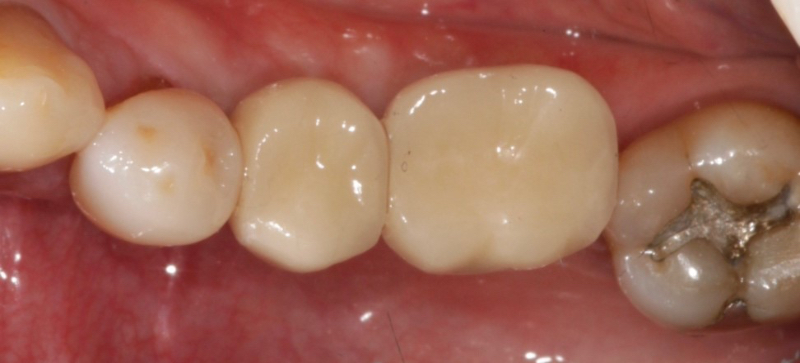

Cement-retained implant restorations consist of an abutment upon which the implant crown is cemented. Abutments can be prefabricated “stock” or custom.

One advantage of a custom abutment is that the margins can be modified to create a supragingival interface between the implant crown and the abutment. This helps make it easier to remove excess cement. Cement-retained implant crowns are often considered more esthetic than screw-retained implant crowns since the cement-retained implant crown does not have an access hole.